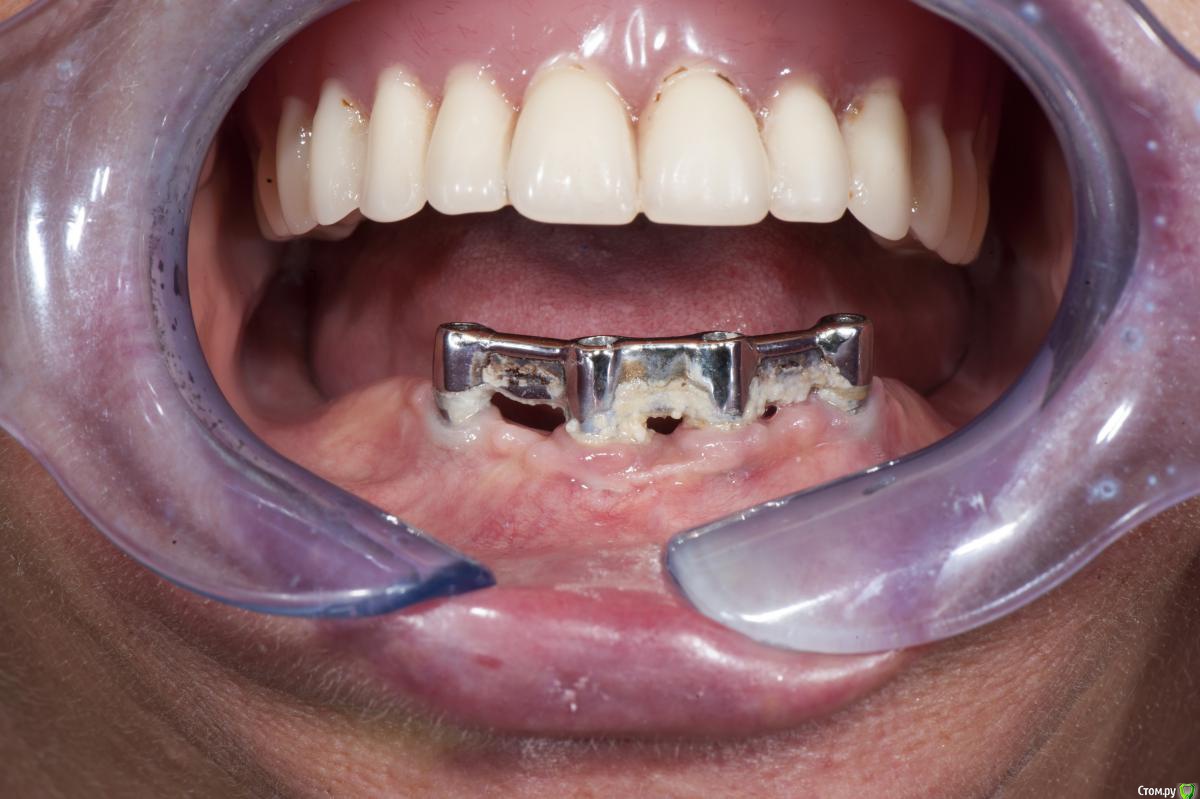

dantist_movani Опубликовано 4 февраля, 2017 Поделиться Опубликовано 4 февраля, 2017 Одна из первых работ. Импланнтаты Niko Leader. Пациент 1949 г.р. Ссылка на комментарий

syrovovec Опубликовано 5 февраля, 2017 Поделиться Опубликовано 5 февраля, 2017 (изменено) Вась за гигиену поругай пациента.. ровненько поставил, молодец)) Изменено 5 февраля, 2017 пользователем syrovovec Ссылка на комментарий

Doc Опубликовано 5 февраля, 2017 Поделиться Опубликовано 5 февраля, 2017 А это вот сегодня. Гигиена, кажется, хромает, но стоят почему-то. Ссылка на комментарий